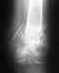

Здравствуйте, мне 27 лет, нахожусь в Таиланде, 6 мая в результате падения сломал правую ногу, врачи диагностировали открытый перелом обеих костей голени.

Доктора ближайшей больницы оказали первую помощь, сказали что нужна операция по восстановлению костей. По сраховке был направлен в другую больницу, где доктор-ортопед сказал, что сначала необходимо наложить гипс и ещё раз сделать рентген. После рентгена он сообщил, что кости встали на место и со временем срастутся. Теперь дело только в открытой ране, которая должна зажить без заражения на антибиотиках. Сейчас, 9 мая, лежу в больнице с гипсом на ноге, под капельницей(питательный раствор, несколько раз в день антибиотики), за это время успел по эл. почте проконсультироваться с врачем из прошлой поликлинники, который настаивает что при переломе обеих костей голени операция необходима. Подсказал, что подобное отношение к травме может быть навязано лечащей клинике страховой компанией, для сокращения затрат. Прошу помочь консультацией по вопросу - обязательна ли операция при таком переломе как у меня. Прикрепляю рентген перелома сразу после травмы и фотографию самой раны. Буду благодарен за любую помощь. http://i011.radikal.ru/1205/0c/41cb3c3da923.jpghttp://s019.radikal.ru/i606/1205/fb/515a9d98cbf6.jpg

Операцию, конечно, лучше сделать. Вопрос - когда лучше. Тут определенного одного ответа нет. Можно оперировать было как закрытый перелом. Можно и подождать заживления раны. Можно и оперировать как открытый перелом, в два этапа - санчала аппарат, а после заживления раны - внутренняя фиксация.